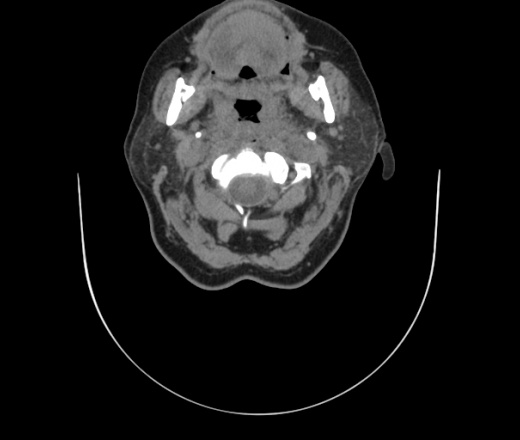

Женщина поступила в х/о спустя 4 дня после того как при употреблении карася подавилась костью.

Наличие газа в средостении на протяжении тел С2-С6 (медиастинальна эмфизема); рыбная кость на уровне тела С6.

При всем уважении, но говорить о медиастинальной эмфиземе, оценивая мягкие ткани шеи, как-то слишком резко. На мой взгляд, это ретрофарингеальное пространство.

Эвакуировали почти 100мл гноя. Но кость не смогли найти. Думаю что она даст дальнейшее ослоднение. Эндоскопически за черпалонадгортаной звязкой не смогли зайти в пищевод, все мягкие ткани отечные, просвет пищевода сдавлен. По всей видимости параэзофагеальная клетчака тоже задействована. Эмпиема, если ее можно так назвать, незнаю как правильно дошла до уровня яремной вырезки. Чем закончиться напишу. Ждем медиастинита.

Флегмона заглоточного пространства шеи, только операция, флегмоны вскрывают. Риск медиастинита.

Согласен с Вами; конечно, наличие газа в клетчатке ретрофарингеального пространства (затмение с опечаткой..). К сожалению, процесс "продвигается" к медиастиниту. Но почему никто, не отмечает наличие рыб. кости; или это для Всех очевидно?

Так вы уже отметили. Хотя ориентировал бы не скелетотопически, а на перстнечерпаловидный сустав.

Кость то мы сразу выявили, размеры где то 17*2мм, но ее так и не получается найти в этой каше